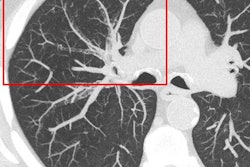

Photon-counting detectors offer significant benefits, along with challenges. Image courtesy of Norbert Pelc, ScD.Photon weighting